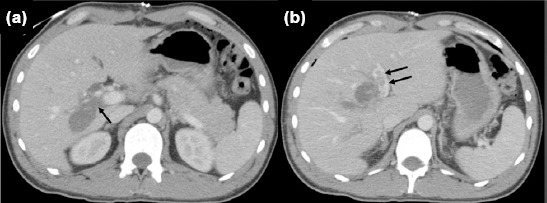

This report describes the successful treatment (without hepatectomy) of a patient who underwent laparotomy and bullet removal for a gunshot injury to the liver at another institution. The patient was later referred for hemobilia and was found to have an un-recognized tangential injury to the right portal vein branch, resulting in portal vein thrombosis, diagnosed on the twelfth day after injury. The patient subsequently developed severe cholangitis. Hepatic arteriography did not identify the source of hemobilia. Fol-lowing thrombectomy of the main portal vein and its left branch, along with portal vein repair, bilateral external biliary drainage from the common hepatic duct was performed. Hemobilia ceased after portal revascularization. A low-volume biliary fistula developed in the early postoperative period but resolved within 17 days with gradual removal of abdominal drains. The patient experienced no further complications during six months of follow-up. Standard biochemical blood tests remained within normal limits, except for slightly elevated alkaline phosphatase (167 U/L: 40-129) and gamma-glutamyl transpeptidase (100 U/L: 8-61) levels. Follow-up contrast-enhanced computed tomography scans on postoperative day 10 and at six months confirmed patency of the main portal vein and its left branch. Additionally, right lobe atrophy and left lobe hypertrophy were observed. In conclusion, applying principles from elective hepatopancreatobiliary surgery to trauma care, and avoiding major hepatectomy in the setting of severe cholangitis, played a crucial role in achieving a successful outcome.